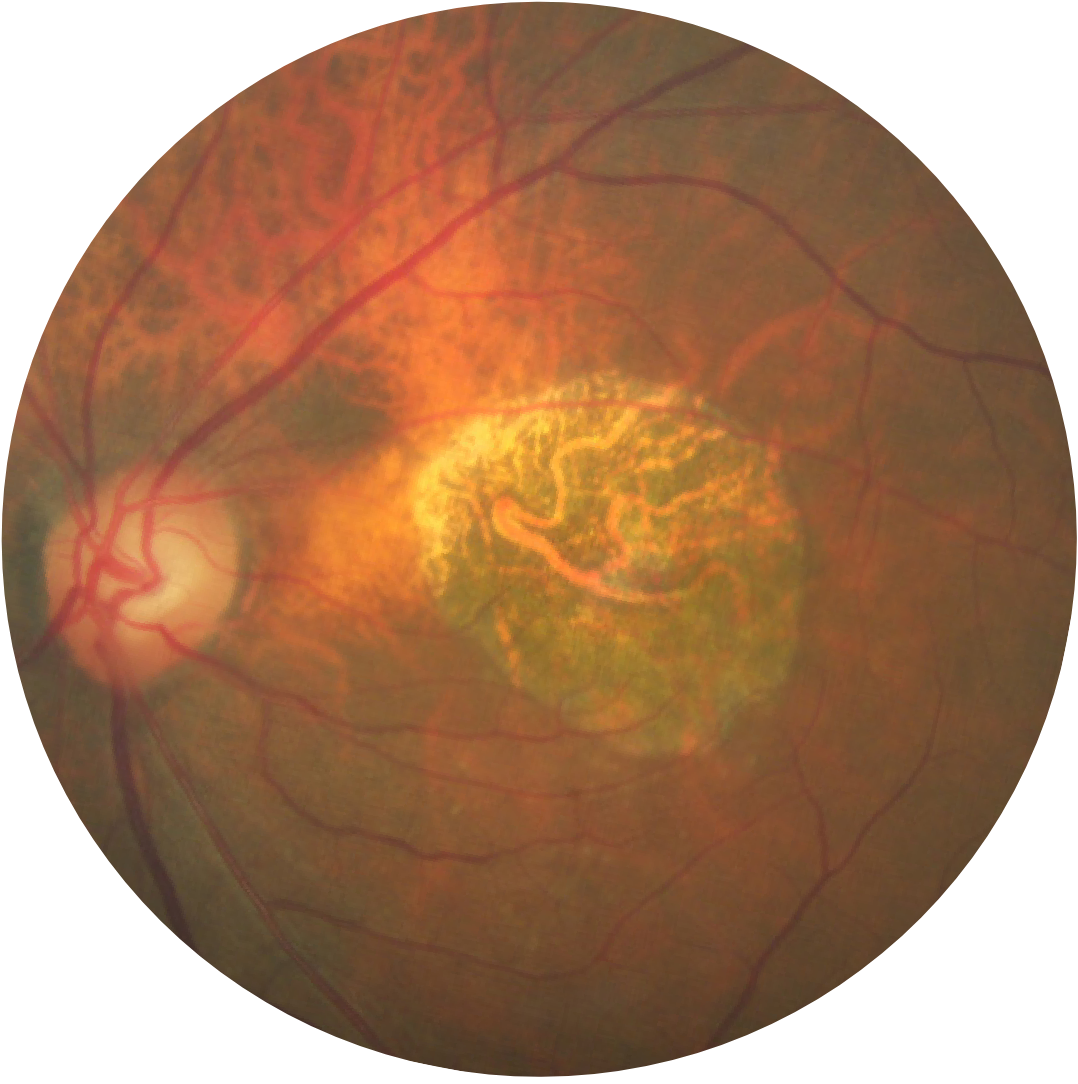

Fundus photograph of a healthy eye

Fundus photograph of an eye with geographic atrophy

Geographic atrophy is characterised by progressive and irreversible loss of the photoreceptors, retinal pigment epithelium (RPE) and underlying choriocapillaris.1,2

Regions of atrophy typically start outside the fovea and expand to involve the fovea, which – over time – leads to permanent loss of vision.1